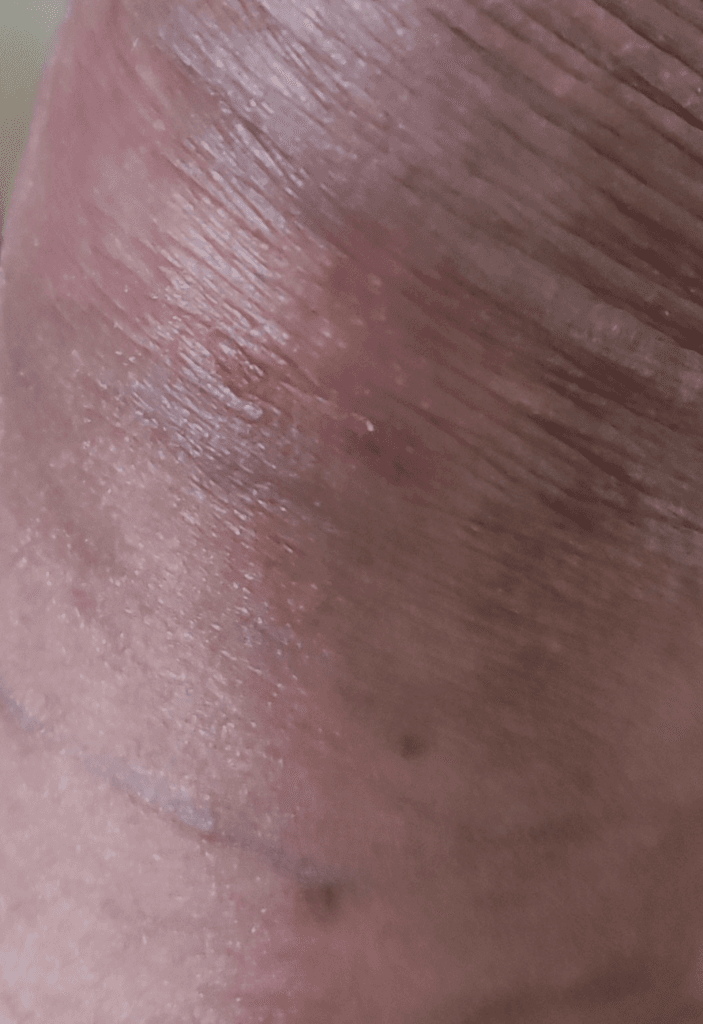

노포경 상태의 남자입니다. 요도염 중상 후에 귀두 앞 부분이 부풀어 오른 후에 귀두 입구와 닿아있는 표피에서 발진이 일어났습니다.

발진이 일어나긴 했는데 가렵지는 않고 하루에 한 두 번정도 따끔거리는 증상이 일어나긴 하는데~

이 것이 헤르페스인지 아니면 다른 병변인지 궁금합니다.

마지막 성관계는 2월 17일입니다.

• 1번 째 사진

사진의 소견을 통해서 헤르패스가 강력하게 의심되거나 하진 않으며 염증 소견이 보이긴 합니다. 관련하여서는 방치를 하거나 하지 마시고 비뇨의학과에 다니면서 치료를 하시는 것이 안전하겠습니다.